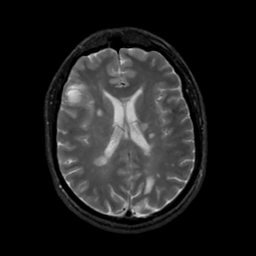

MR Study #6, March 17, 1991 -- Slice #30